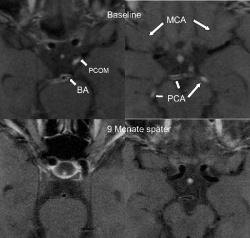

untersucht wurde. Die Pfeile zeigen auf die Kontrastmittelaufnahme in den entzündeten Arterien, die sich unter immun-

suppressiver Therapie nach 9 Monaten vollständig zurück bildet